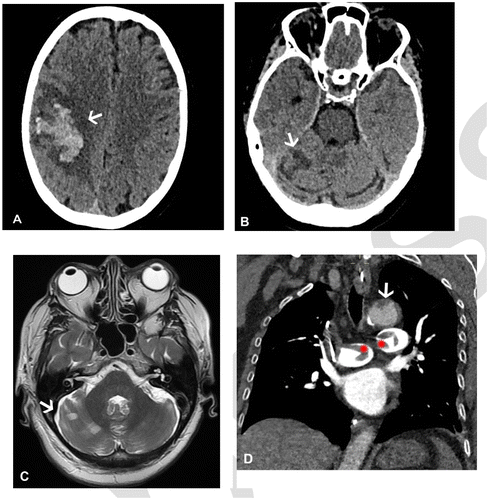

Could the emerging artificial intelligence platforms Saige-Dx and Quantib Prostate 2.0 improve cancer detection with mammography and prostate MRI?